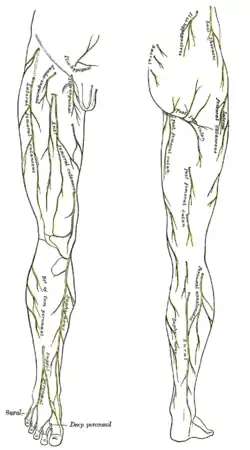

Plan of lumbar plexus. Cutaneous nerves of the right lower extremity. Front and posterior views.

Cutaneous nerves of the right lower extremity. Front and posterior views.